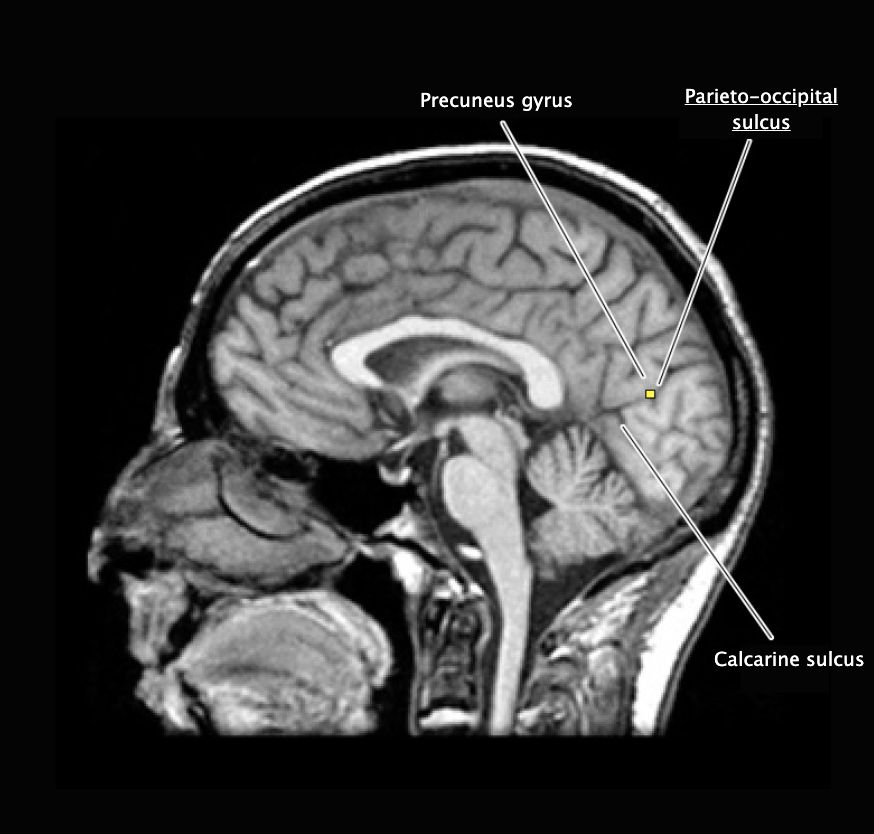

Calcarine sulcus

A prominent sulcus in the medial occipital lobe formed by the cuneus and lingual gyral structures; this sulcus extends roughly horizontally from the parieto-occipital sulcus to its termination in the occipital pole. The calcarine sulcus contains the primary visual cortex (also called the "striate cortex").

Parieto-occipital sulcus

Prominent vertically oriented sulcus on the medial aspect of the hemisphere that divides the parietal and occipital lobes; intersects the anterior terminus of the calcarine sulcus at nearly a right angle.

Primary visual cortex

Cortical area (Brodmann's area 17; also referred to as the "striate cortex") in the banks of the calcarine sulcus that first receives visual signals from the relevant thalamic nucleus (lateral geniculate nucleus).